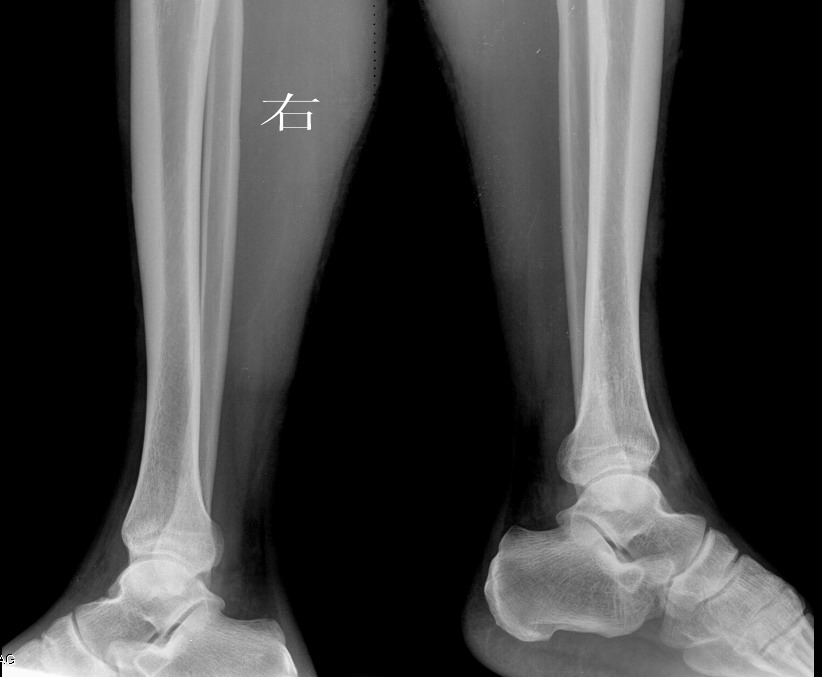

大家帮忙看下左胫骨下段外侧是骨膜反应还是骨间膜改变,或者其它病变

例1、女,48岁,以外伤就诊

双侧对比应该有

是不是拍片的时候病人不稳定所致?正侧位综合观察未见明显异常。